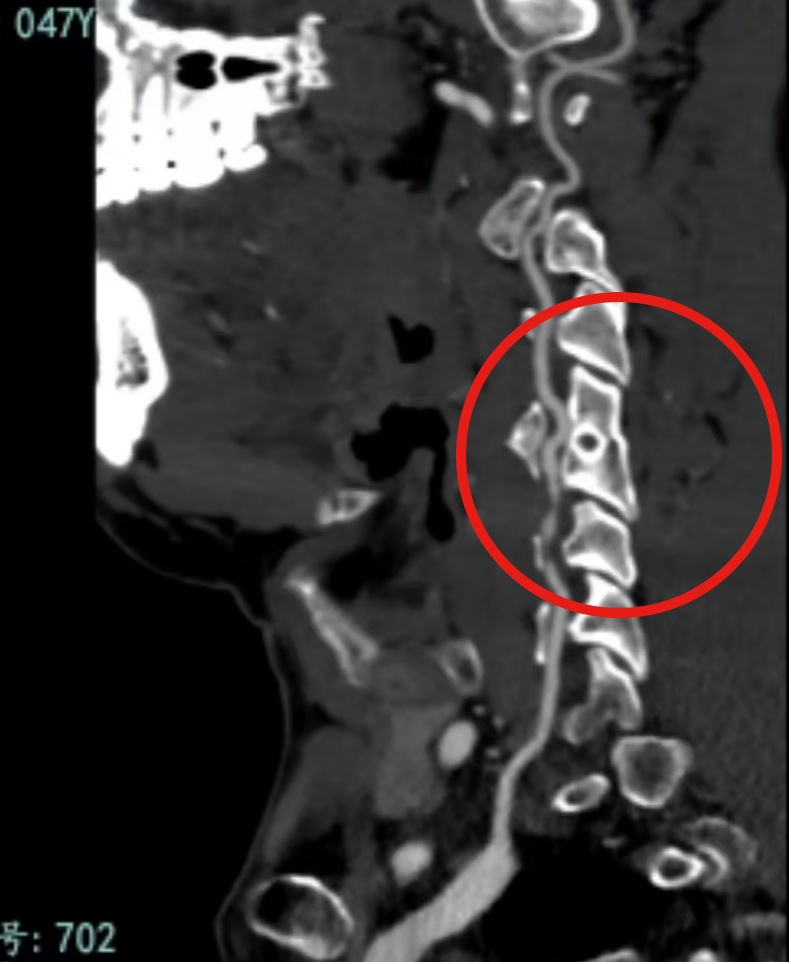

紧接着的颈部CTA更揪紧了众人的心:右侧椎动脉V2段出现夹层样改变,如同即将引爆的“定时炸弹”。之后,通过脑血管造影,确诊他患上右侧动脉夹层。

张先生的椎动脉因外力挤压出现内膜撕裂,血液渗入血管壁形成血肿,既造成血管狭窄,又产生血栓,脱落的栓子直接堵死了小脑供血血管。所幸,经过紧急治疗,张先生的血管逐渐修复,一周后已能独立行走,但他仍需长期随访防止复发。